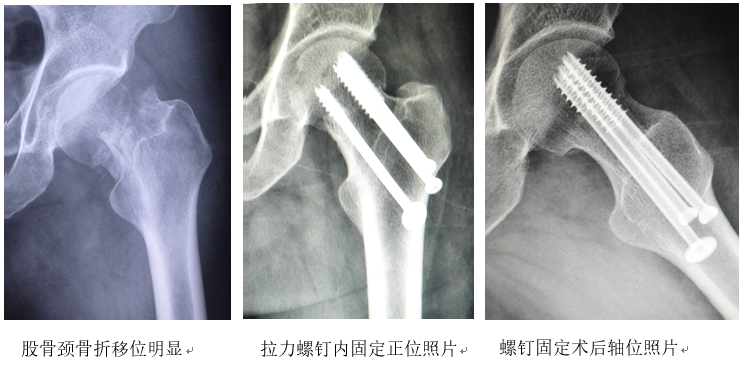

查体:跛行步态,左髋短缩、内收、内旋畸形,腹股沟有压痛和纵轴叩痛,舌稍暗红,苔稍黄,脉弦。照片显示左股骨颈头下骨折,骨折远端向外、上移位明显。

医生介绍了最为适宜的闭合复位螺钉内固定、全髋关节置换这2种手术方案及其利弊,患者选择第一方案。入院第3天,在全麻下实施了股骨颈骨折手法整复及螺钉内固定术:将左下肢固定在牵引架上,内收位牵引,逐渐外展,复位者双手拇指向内、下方挤压股骨大转子,透视见骨折对位及颈干角、前倾角恢复良好。再于股骨大转子外下切开2个2厘米长切口,横截面呈倒“品”字形平行拧入3枚拉力螺钉,透视证实其位置良好。术后穿丁字鞋,适当活动膝、踝,下肢行空气压力波治疗。术后服桃红四物汤加味以行气消瘀,每日1副。

手术次日髋部疼痛开始缓解,床边照片骨折固定位置稳定;术后1周髋部疼痛基本消失,左下肢无明显肿胀;术后2周,左髋无明显压痛,舌淡红,苔薄白,脉缓,照片复查正常,中药治则改为接骨续损,用接骨紫金丹口服,切口拆线,出院;术后2个月改服六味地黄丸以补肾壮骨;手术后3个月照片复查,股骨颈骨折线模糊,内固定位置无变化,开始扶双拐下地行走;术后半年弃拐行走,恢复正常活动;术后2年随访无股骨头坏死。